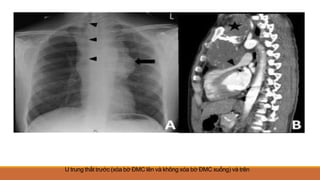

U trung thất trước (xóa bờ ĐMC lên và không xóa bờ ĐMC xuống) và trên

U trung thấttrước (xóa bờ ĐMC lên và không xóa bờ ĐMC xuống) và trên